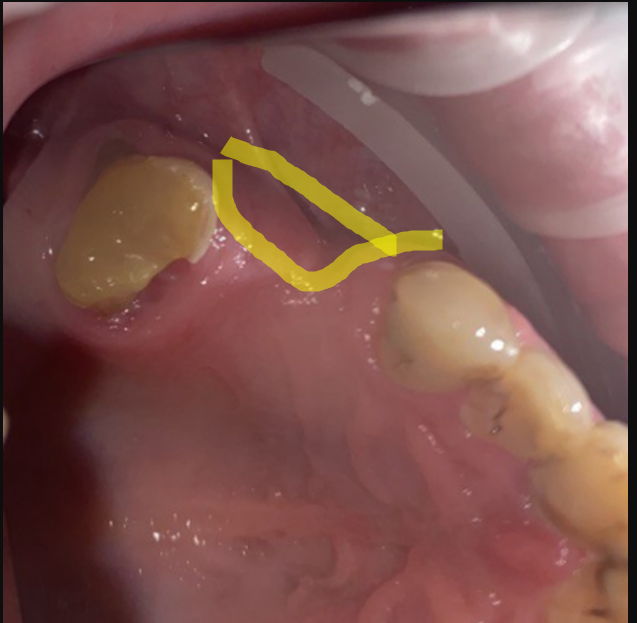

It'sGeorgy Опубликовано 28 мая, 2021 Поделиться Опубликовано 28 мая, 2021 Здравствуйте. 21.05.21: Язычносмещенный разрез, удаление оставленного корня 2.4, удаление 2.6 и 3.8. Имплантаты 2.4, 2.5. Пошел сделал снимок: Не понравился дистальный наклон 2.5, пошел перекручивать. Пока крутил-вертел торк с 25 упал до пальцевого. Принял решение установки коротких формиков, ССТ вестибулярно и ушивания наглухо. Сегодня пациент пришел на осмотр к другому доктору, а там вот такая печалька: Какие ошибки предполагаю сам: 1. Слишком толстый трансп, ушивание которого вызвало перенатяжение 2. Медиальный шов, который держит трансп совсем хиленький и, на самом деле, мало что держит. И главный вопрос: что делать? Оставлять и надеяться, что что-то приживется или полностью убирать? Ссылка на комментарий

It'sGeorgy Опубликовано 29 мая, 2021 Автор Поделиться Опубликовано 29 мая, 2021 (изменено) Всем спасибо за отклик. Через 2 мес, если не забуду, выложу фото результата. 28.05.2021 в 22:17, АнтонТЛТ сказал: Какой смысл в свободном трансплантате был? По плану было увеличить объем вестибулярно и толщину окклюзионно, чтобы в дальнейшем, на этапе времяшек, дополнительно сместить все в сторону этого дефекта, чтобы его закрыть: 11 часов назад, Женька сказал: Не слишком ли высоко трансплантат забран? не критикую, только интересуюсь. Сложно сказать. При заборе трансп с неба я иглой во время анестезии смотрю участок, где достаточная толщина. Вероятно, в момент операции, эта область показалась наиболее перспективной с этой точки зрения. Сейчас, как сказал @Карен Аванесов , я бы вообще с бугра взял. Да и в целом, с десной бы работал на этапе высоких формиков. Изменено 29 мая, 2021 пользователем It'sGeorgy Ссылка на комментарий

It'sGeorgy Опубликовано 12 июня, 2021 Автор Поделиться Опубликовано 12 июня, 2021 Прошу прощения, что долго не получилось ответить. 03.06.2021 в 00:11, АнтонТЛТ сказал: Я правильно понимаю, что установлены короткие фдм, подшит трансплантат, не было мобилизации и рана ушита наглухо? Верно. 03.06.2021 в 00:11, АнтонТЛТ сказал: Если да, то за счёт чего получилось ушить наглухо? Выходит, что за счет излишнего натяжения. Но, во время операции, мне не показалось, что я сильно что-то тягу. 03.06.2021 в 00:11, АнтонТЛТ сказал: Трансплантат получается не вестибулярно, а окклюзионно пришит. Да. В целом, хотел, чтобы было так: Трансп лежит частично над имплантатами, частично - вестибулярно под лоскутом. Лоскут фиксируется небно . 03.06.2021 в 00:11, АнтонТЛТ сказал: Трансплантат фиксирован обычным П-образным швом? Да, двумя. 03.06.2021 в 00:11, АнтонТЛТ сказал: Есть фото со швами? К сожалению, нет. Вот так вот это выглядело вчера. По-моему, десна возвращается в состояние, которое было до операции. Дальше по плану долгожданная чистка + коррекция домашней гигиены и лечение всего того, что надо полечить. Через 1.5 мес буду открывать имплантаты и устанавливать высокие формики и думать, что дальше. Ссылка на комментарий